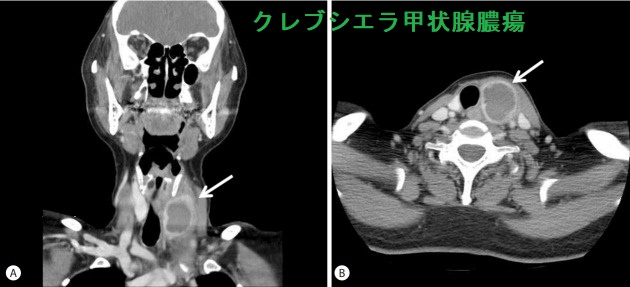

クレブシエラ甲状腺膿瘍 造影CT画像;リング状増強がくっきり。甲状腺膿瘍は甲状腺超音波(エコー)検査より造影CT検査の方が有用かもしれません。[Clin Mol Hepatol. 2018 Mar;24(1):88-91]

糖尿病やその他の免疫不全の無い健康な55歳の女性が、クレブシエラ・ニューモニエ(Klebsiella pneumoniae)による肝膿瘍、甲状腺膿瘍と化膿性内眼球炎(内因性眼内炎)を起こした報告があります。[Clin Mol Hepatol. 2018 Mar;24(1):88-91]。

クレブシエラ菌のクレブシエラ・ニューモニエ(Klebsiella pneumoniae、肺炎桿菌)はグラム陰性桿菌で、急性化膿性甲状腺炎と甲状腺膿瘍の起因菌。[Endocrinol Diabetes Metab Case Rep. 2020 Nov 26;2020:EDM200137.][J Diabetes Investig. 2016 Jan;7(1):127-9.]